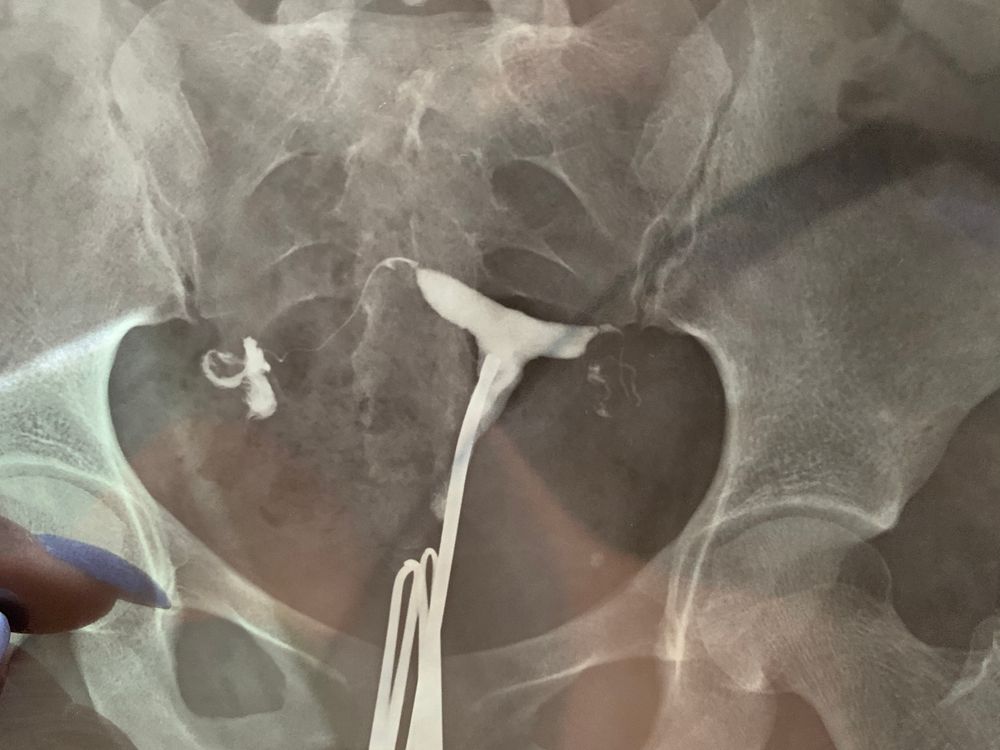

Гистеросальпингография: описание и фотографии